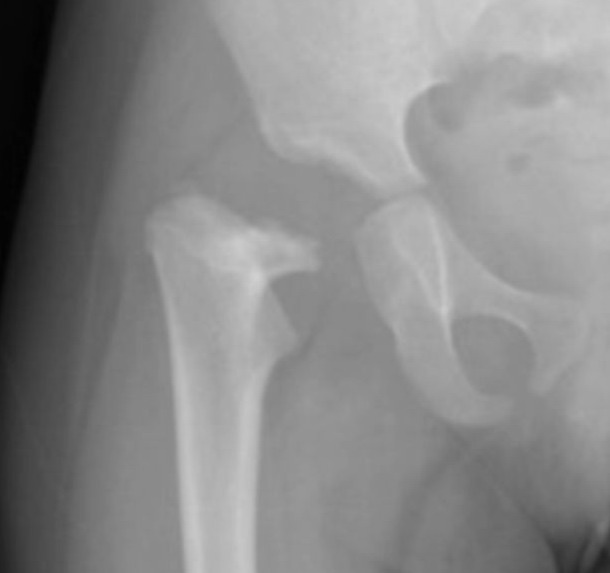

以下是引用jinguoji在2008-6-30 14:57:00的发言:[br]支持右股骨颈坏死伴髋关节脱位。

以下是引用jiangjing在2008-6-30 17:13:00的发言:[br]股骨头骨骺缺血性坏死,伴脱位

以下是引用wjyd在2008-7-2 14:41:00的发言:[br]股骨头坏死移位伴髋关节脱位